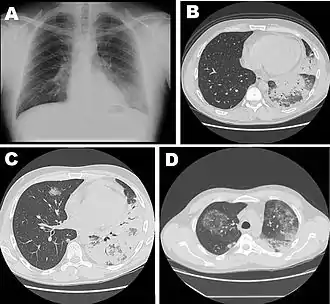

| Chest X-ray of a severe case of legionellosis upon admission to the emergency department | |

Laboratory tests may show that kidney functions, liver functions, and electrolyte levels are abnormal, which may include low sodium in the blood. Chest X-rays often show pneumonia with consolidation in the bottom portion of both lungs. Distinguishing Legionnaires' disease from other types of pneumonia by symptoms or radiologic findings alone is difficult; other tests are required for definitive diagnosis.